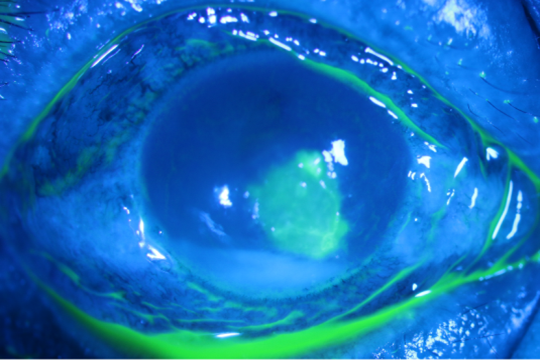

金秋九月,又到了收获的季节,玉米、花生、稻谷等农作物纷纷成熟。忙碌的秋收季节,在农作物收获过程中,容易突发玉米叶划伤眼睛、泥土溅入眼等情况,植物及泥土中携带大量真菌,进入眼睛后容易诱发眼部真菌感染。病例分享陈阿姨(化名)10天前在地里收花生时,花生上的泥巴不慎渐入右眼,出现了左眼眼红、眼痛、流泪的症状,第2天开始出现右眼视力下降,并逐渐加重。去当地医院检查,当地医生怀疑“右眼真菌性角膜炎”,开了氟康唑眼药水点眼。局部用药之后,陈阿姨眼部症状并没有任何缓解,症状甚至逐渐加重,遂至山东第一医科大学附属青岛眼科医院就诊。检查发现,陈阿姨右眼视力下降到只能看到手动,角膜中央偏下方溃疡,合并前房积脓,共焦显微镜查见大量菌丝,确诊为“右眼真菌性角膜溃疡”。入院时角膜中央区偏下方浸润混浊,前房积脓共焦显微镜检查发现角膜基质中大量真菌菌丝通过右眼抗真菌药伏立康唑滴眼液频繁点眼以口服伏立康唑控制感染,用药2天后,前房积脓基本消失,但角膜浸润仍重。为了进一步控制感染,经过患者和家属同意,施行了右眼角膜清创术,清除病变的角膜,并在手术中取病变角膜组织进行真菌培养。术后第1天,右眼视力渐渐恢复,角膜水肿及基质浸润明显减轻。在手术中进行的真菌培养,显示为镰刀菌感染,对伏立康唑敏感。陈阿姨术后继续抗真菌治疗,无复发迹象。术后第1天,角膜水肿及基质浸润相比术前明显减轻陈阿姨在进行一次角膜清创后,角膜真菌感染比较幸运地控制住了,而许多患者由于不重视植物性角膜外伤,未及时就医,导致感染加重,严重的需要进行角膜移植甚至摘除眼球。真菌性角膜炎是感染性角膜炎中较为棘手的一种,多与植物性外伤有关。早期抗真菌药物治疗可发挥较好的抗感染作用,一旦感染进展,药物治疗效果欠佳,大多需要进行手术治疗。一旦发生植物性外伤,建议及时到医院就诊,并密切随诊观察病情变化,避免延误病情造成不可逆的视力损伤。